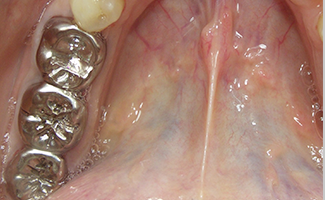

①ファイバーポスト

②金属ポスト

進行した虫歯では、神経や虫歯になった歯を取り除き、土台を入れずにかぶせ物治療をしても、空洞ができ、すぐ外れてしまいます(下図参照)。

そこで歯の土台になる部分(これをポストといいます)を作ります。その材料には①ファイバーポスト、②金属ポストがあります。

特徴 2

私たちの歯は、光りを良く通すため、白く明るくしかも自然な透明感もあります。しかし、金属製のポストは全く光を通しませんので、歯肉と歯の境目が暗く不自然になってしまいます。

ところが、ファイバーポストは歯のように光を通すのでとても自然な感じになります。(上写真)さらに金属イオンにより歯肉がやせたり、黒ずむのも防ぐことができます。